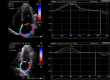

Purpose: Atrial fibrillation (AF) and diabetes mellitus (DM) are common pathogenic diseases. Diabetes is an independent risk factor for AF, and coexisting AF is a risk factor for the diabetic pa-tient's progression. The purpose of this study was to see if two-dimensional-speckle tracking echocardiography (2D-STE) might provide valuable criteria for determining the risk of AF in diabetic patients.

Patients and methods: This retrospective study compared 30 adult diabetic patients with documented paroxysmal atrial fibrillation (PAF) with 30 age- and sex-matched diabetic patients without PAF. Inclusion criteria were: age ≥18 years, sinus rhythm, diabetes mellitus type 2, and the ability to sign the informed consent. Exclusion criteria included: moderate or severe valvular disease, previous myocardial infarction, left ventricular ejection fraction (LVEF) <50%, congenital heart disease, a history of cardiac surgery, paced atrial or ventricular rhythm, inadequate echocardiography imaging. The medical history, clinical, biochemical data and the results of the transthoracic cardiac ultrasound examination were registered during their evaluation at the outpatients cardiology clinics.

Results: The mean age of the patients was 62.5±1.7 years, 60% were men. Diabetic patients who experienced PAF episodes demonstrated significantly impaired left atrial (LA) deformation patterns, with decreased LA strains and increased LA stiffness (p < 0.05).

Conclusion: The present study demonstrates that LA strains and LA stiffness are significantly associated with the occurrence of PAF in diabetic patients. As 2D-STE of the LA is more sensitive than routine echocardiographic examination, it should be performed in patients suspected of being suffering from PAF.